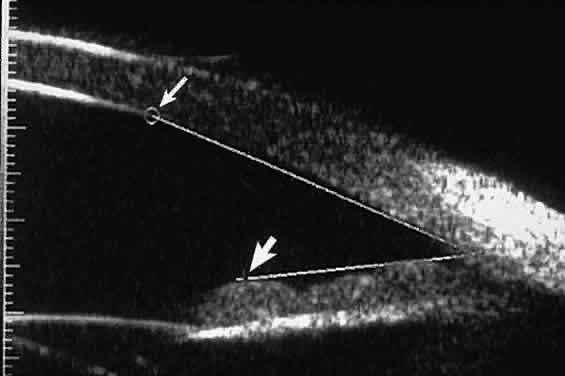

certain patients with open-angle glaucoma, UBM can provide

information that may be of some diagnostic value (Fig. 10). For example, in pigment dispersion syndrome (see Fig. 10A),6 UBM typically reveals posterior bowing of the peripheral iris (“q” configuration

of peripheral iris by Spaeth classification5). In plateau iris syndrome (see Fig. 10B),7 UBM usually reveals abnormally steep anterior angulation of the peripheral

iris (“s”configuration of peripheral iris by Spaeth classification5), insertion of the iris from the anterior ciliary body, and retroiridic

projection of the ciliary processes. In eyes with peripheral anterior

synechiae (see Fig. 10C and D), UBM can reveal the extent of iridocorneal adhesion even if the cornea

Fig. 10. UBM features of special glaucoma cases. A. Pigment dispersion syndrome with posterior bowing of peripheral iris (“q” configuration by Spaeth gonioscopic grading system). B. Plateau iris syndrome with origin of iris from anterior surface of ciliary

processes behind peripheral iris, slitlike narrowing of peripheral

angle, and abrupt transition from steep peripheral iris to flat iris

midzone. C. Broad peripheral anterior synechia with posterior bowing of nonadherent

iris. D. Peripheral anterior synechia with aqueous-filled slit between site of

iridocorneal adhesion and iris root after cataract extraction with implantation

of posterior-chamber IOL. Fig. 10. UBM features of special glaucoma cases. A. Pigment dispersion syndrome with posterior bowing of peripheral iris (“q” configuration by Spaeth gonioscopic grading system). B. Plateau iris syndrome with origin of iris from anterior surface of ciliary

processes behind peripheral iris, slitlike narrowing of peripheral

angle, and abrupt transition from steep peripheral iris to flat iris

midzone. C. Broad peripheral anterior synechia with posterior bowing of nonadherent

iris. D. Peripheral anterior synechia with aqueous-filled slit between site of

iridocorneal adhesion and iris root after cataract extraction with implantation

of posterior-chamber IOL.